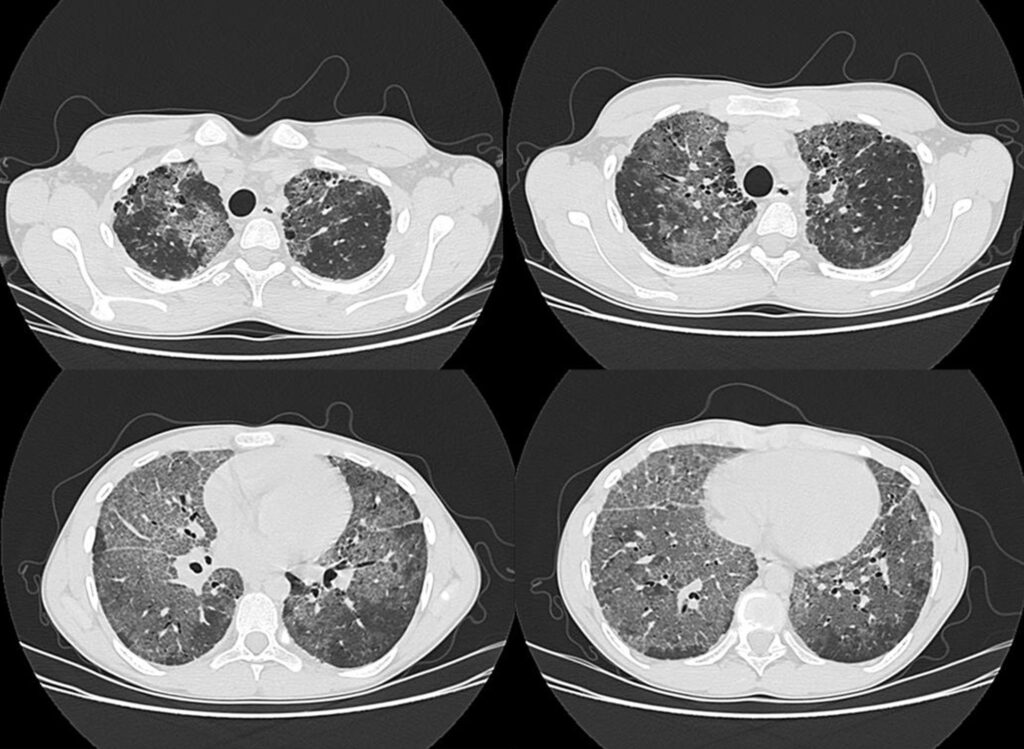

La tomografía computada de alta resolución constituye una técnica radiológica avanzada que se ha consolidado como herramienta de primera elección para el estudio morfológico detallado del parénquima pulmonar y de las vías respiratorias de pequeño calibre. Su fundamento técnico radica en la obtención de cortes extremadamente delgados, usualmente de entre uno y dos milímetros de espesor, con un campo de visión reducido que permite ampliar la imagen al máximo, y utilizando algoritmos de reconstrucción específicos, denominados filtros de alta resolución, que optimizan la nitidez de los contornos estructurales. Esta metodología permite obtener imágenes de gran fidelidad anatómica, en las que se logra una representación casi macroscópica del tejido pulmonar, comparable a la observada en estudios patológicos post mortem.

Gracias a esta precisión, la tomografía computada de alta resolución permite visualizar con claridad componentes anatómicos del lobulillo secundario pulmonar, como los bronquiolos, arterias centrolobulillares, septos interlobulillares y linfáticos subpleurales. Este nivel de detalle resulta fundamental para el reconocimiento de patrones radiológicos característicos de diferentes procesos patológicos que afectan tanto al espacio aéreo como al intersticio pulmonar.

En particular, esta técnica es insustituible en la evaluación de bronquiectasias, ya que permite demostrar la dilatación bronquial, el engrosamiento de las paredes de los bronquios y la presencia de secreciones retenidas. También es especialmente útil en el diagnóstico del enfisema pulmonar, permitiendo identificar y clasificar sus diferentes formas —centrilobulillar, panacinar o paraseptal— mediante la visualización directa de áreas de destrucción parenquimatosa sin repercusión fibrosa. Asimismo, es la técnica más adecuada para el estudio de enfermedades que comprometen las vías aéreas de pequeño calibre, como la bronquiolitis obliterante o las bronquiolitis relacionadas con enfermedades sistémicas o exposiciones ambientales.

No obstante, uno de sus principales campos de aplicación es el estudio de las enfermedades intersticiales difusas del pulmón. Estas entidades, de etiología diversa y frecuentemente compleja, presentan patrones de afectación radiológica que en muchos casos permiten establecer un diagnóstico presuntivo preciso sin necesidad de métodos invasivos. Entre los patrones mejor caracterizados se encuentran el de la neumonía intersticial usual, con su típica arquitectura distorsionada y panalización subpleural basal; el patrón micronodular y peribroncovascular de la sarcoidosis; los quistes de distribución irregular en la histiocitosis pulmonar de células de Langerhans; o las opacidades en vidrio deslustrado con distribución centrolobulillar en la neumonitis por hipersensibilidad.

La tomografía computada de alta resolución no solo permite una evaluación detallada de la extensión y morfología de las lesiones, sino que en muchos casos proporciona información diagnóstica definitiva. En particular, cuando se identifica un patrón clásico de neumonía intersticial usual con panalización, la especificidad del hallazgo es tal que puede evitar la necesidad de realizar una biopsia pulmonar, procedimiento que conlleva riesgos no despreciables y que puede resultar innecesario ante una correlación clínica y radiológica concluyente.